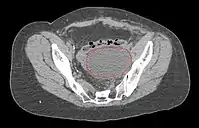

Work-Up

- CT of abdomen/pelvis typically not necessary, unless suspicion of extra-pelvic disease

- MRI is best modality for assessing myometrial invasion and cervical involvement, but provides no additional information if surgery is planned anyway

Lymphocele

- Seen postoperatively in up to 30% of GYN surgeries with pelvic/para-aortic LND

- Believed to arise from surgical transsection or inadequate ligation of draining lymphatics

- Lymphatic fluid may accumulate in various pelvic and retroperitoneal compartments

- Small lymphoceles typically resorb spontaneously

- Large lymphoceles may cause compression symptoms, and may result in abdominal distention, abdominal and pelvic pain, hydronephrosis, bladder dysfunction, constipation, tenesmus, edema of the ipsilateral leg and of the genitalia, and thromboembolism of iliac vessels

- Infection may cause fever, chills, and sepsis

- Symptomatic lymphoceles are typically managed initially with percutaneous CT-guided drainage, surgical therapy may be required

- Postoperative Lymphocele